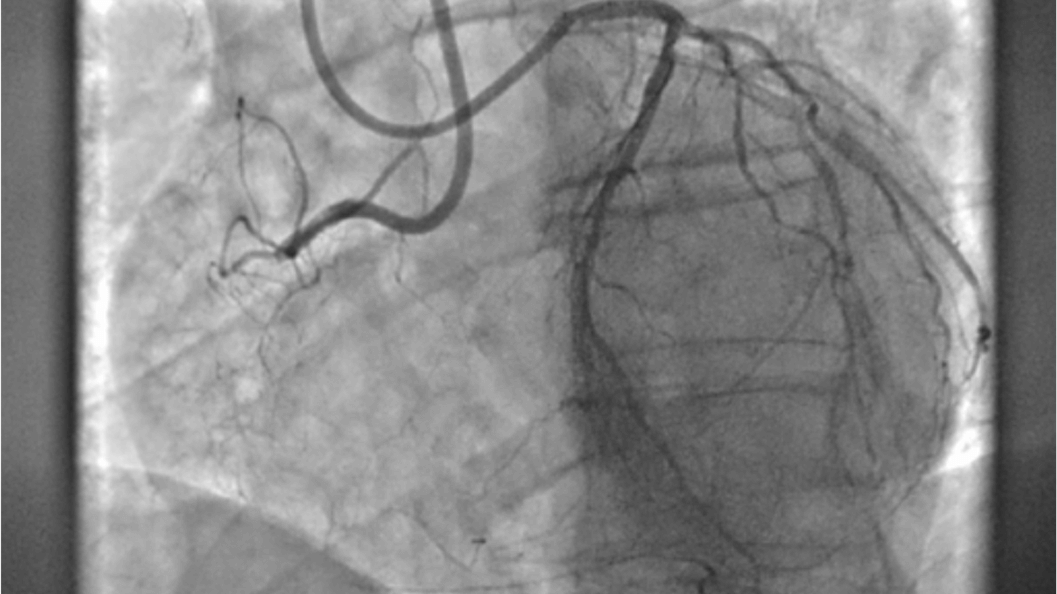

SIGNA™ Champion offre un design modulare con opzioni software e hardware pronte per soddisfare le priorità cliniche. Include strumenti di base e avanzati e soluzioni per la qualità delle immagini come AIR™ Recon DL e Sonic DL™. Queste applicazioni consentono non solo di ottimizzare i casi di routine, ma anche di operare in altri campi specifici come neurologia, apparato muscolo-scheletrico, cardiologia e oncologia. E non è tutto. SIGNA™ Champion è in grado di offrire configurazioni a 32, 48 e 64 canali per garantire la massima flessibilità e semplificare la configurazione delle bobine sulla base delle diverse anatomie.